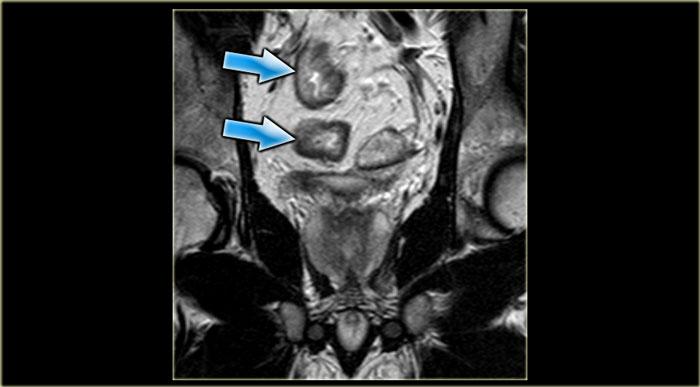

Bên trái là một ví dụ về rò trên cơ thắt.

Có hai đường rò trong vùng hố ngồi-hậu môn.

Đường rò bên phải chạy qua cơ mu-trực tràng (dấu hoa thị) và lỗ mở niêm mạc nằm ở

mức đường lược (mũi tên đen).